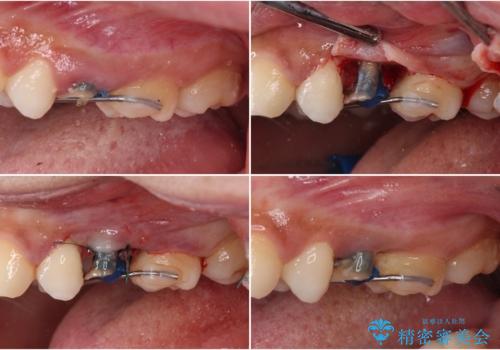

その後骨形成処置を行い、治癒を待って補綴治療を行うこととしました。

外科処置の注意事項(リスク・副作用など)

- 外科手術のため、術後に出血、痛みや腫れ、違和感を伴います

- 口腔内の状態によっては適応できないことがあります